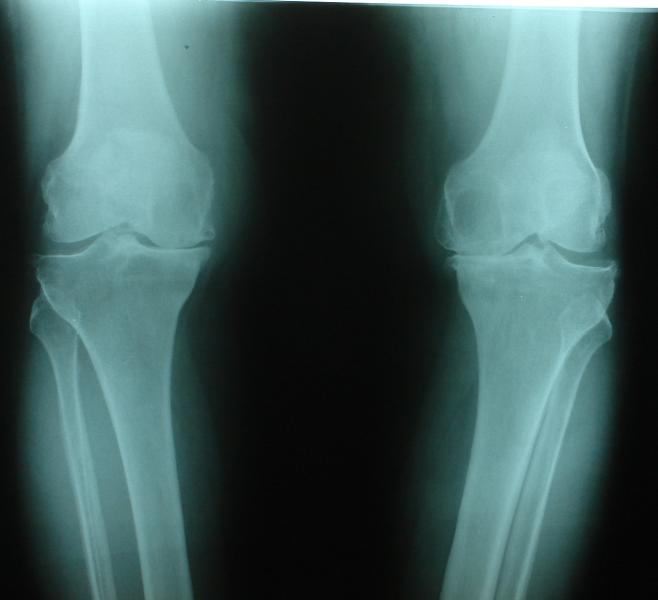

GRADE 4 OSTEOARTHRITIS BOTH KNEE (BEFORE SURGERY)